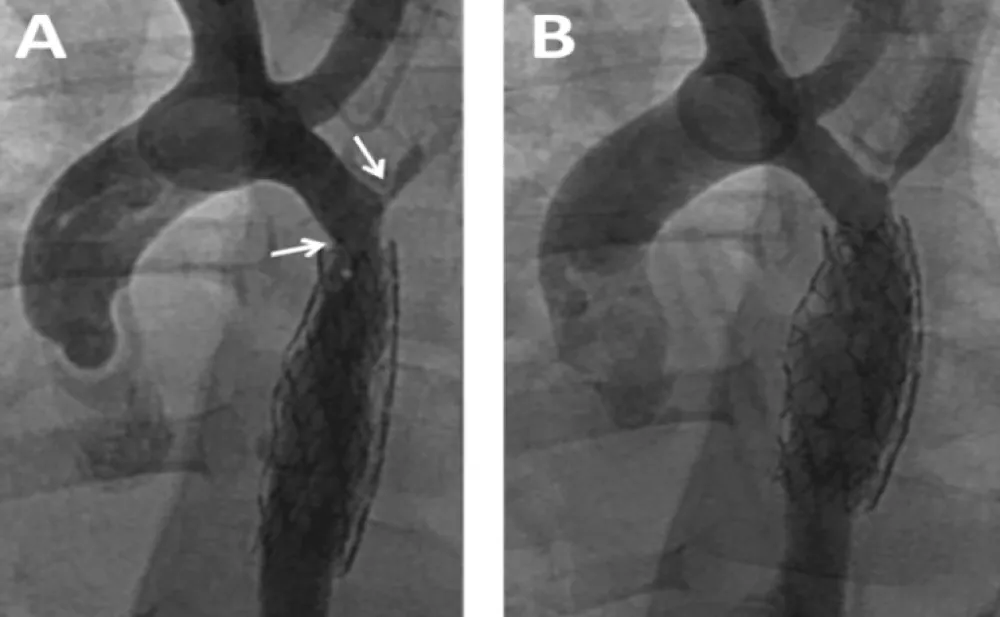

Cardiac catheterization and aortogram for stent angioplasty were performed showing similar diameters to those described in the CT (Figure 2A and B). Pressure measurements are shown in Table 1. The peak systolic gradient across the coarctation decreased markedly after stenting with a 29 mm long Genesis XD stent delivered over a 5F 5 by 30 mm balloon catheter. Control aortogram showed a well expanded stent with a uniform 5 mm diameter similar to that of the descending aorta.

Figure 2: Stenting Procedure for Recurrent Coarctation at age 5 months. A: Pre stenting aortogram shows the coarctation and mid aortic stenosis; B: Post stent angioplasty depicts uniform diameter of the descending aorta from the coarctation site up to the diaphragm level.